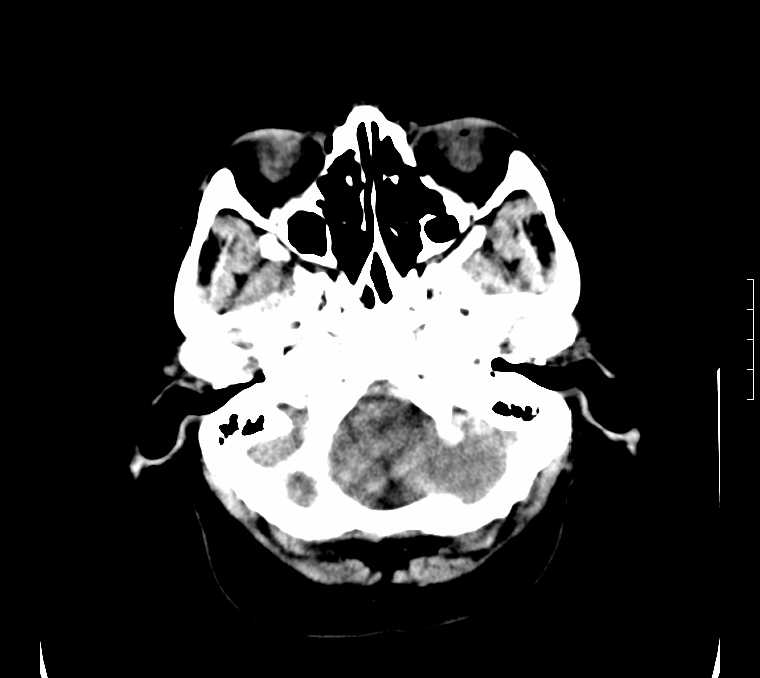

标题: CT24387:看看这例脑部改变!!

老年女性。头晕。

考虑:甲旁减。

fahr病

鉴别于特发性家族性脑血管亚铁钙沉着症(fahr`s病)与甲状旁腺机能低下之间,请结合临床及相关实验室检查。